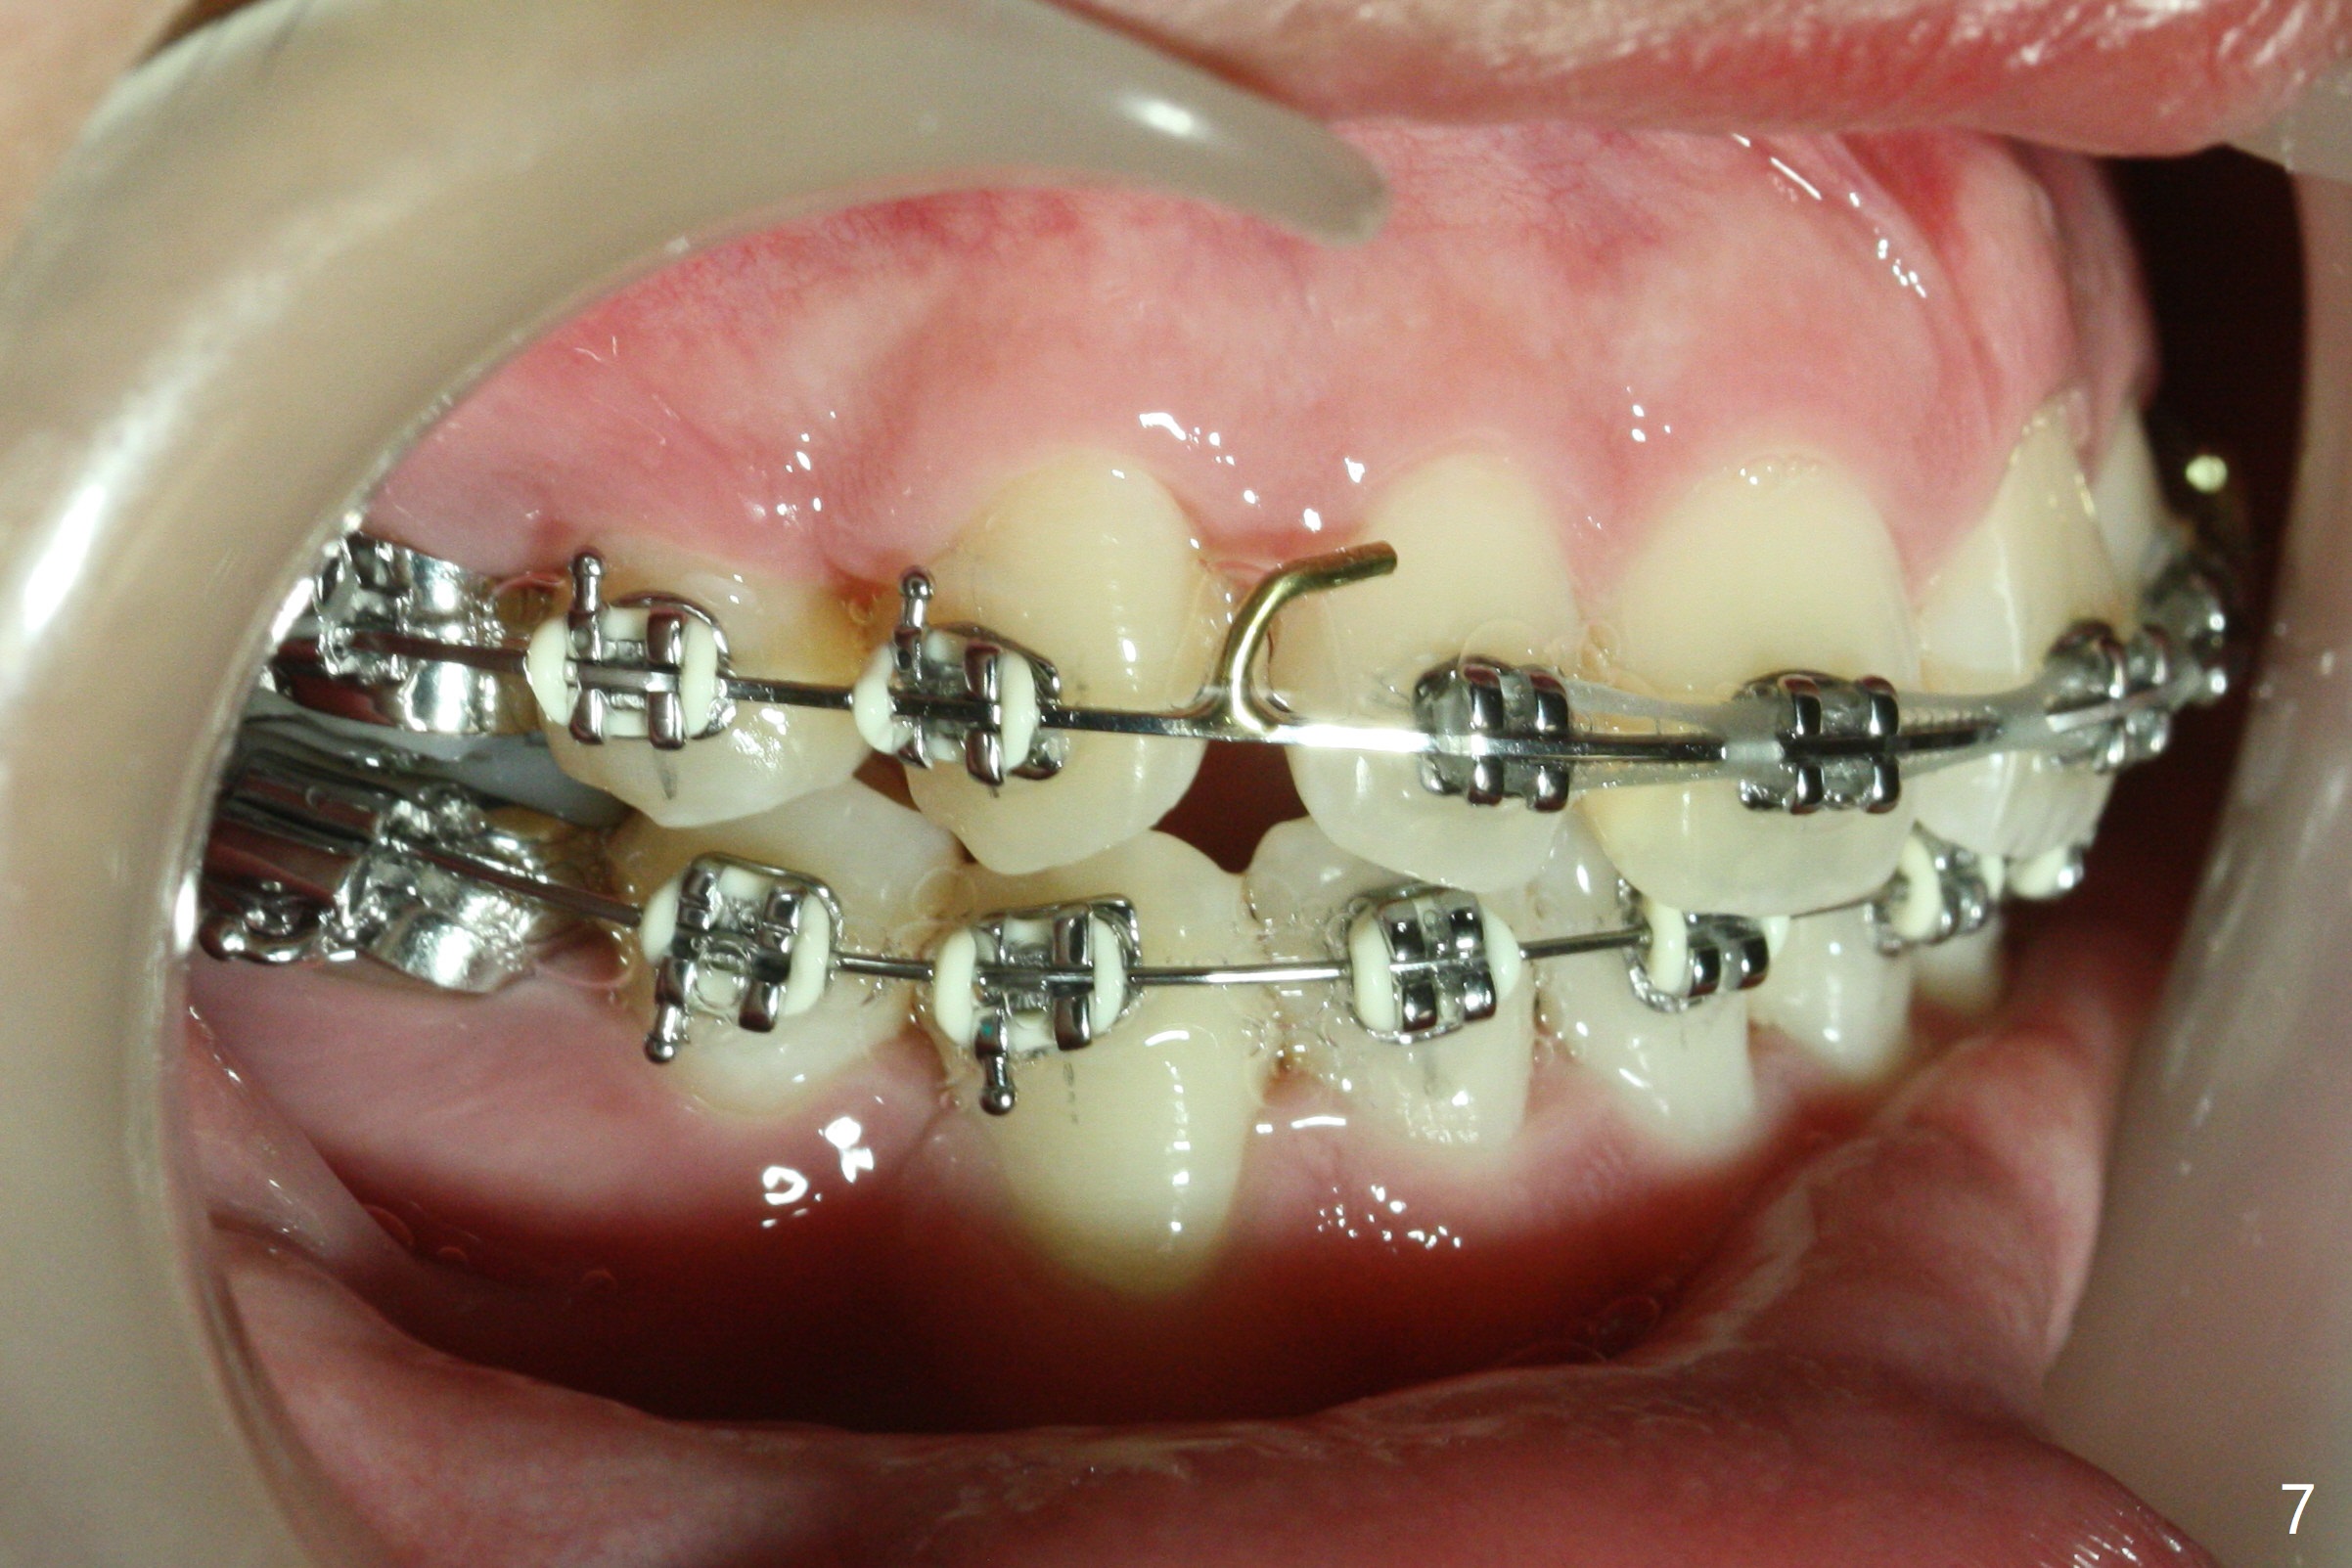

Twelve months post extraction and banding, there is anterior overjet. A posted wire is used to retract the upper incisors for a month. It appears that the upper midline deviates to the right (Fig.6, as compared to Fig.5 (pre-treatment)). Closed coil spring is removed on the right in hope that the upper midline will shift to the normal by the left coil spring (Fig.7-9). Is there a better alternative? There is mild root tip resorption 2 years 1 month post banding/immediate post debanding, as related to extraction ortho (Fig.10).